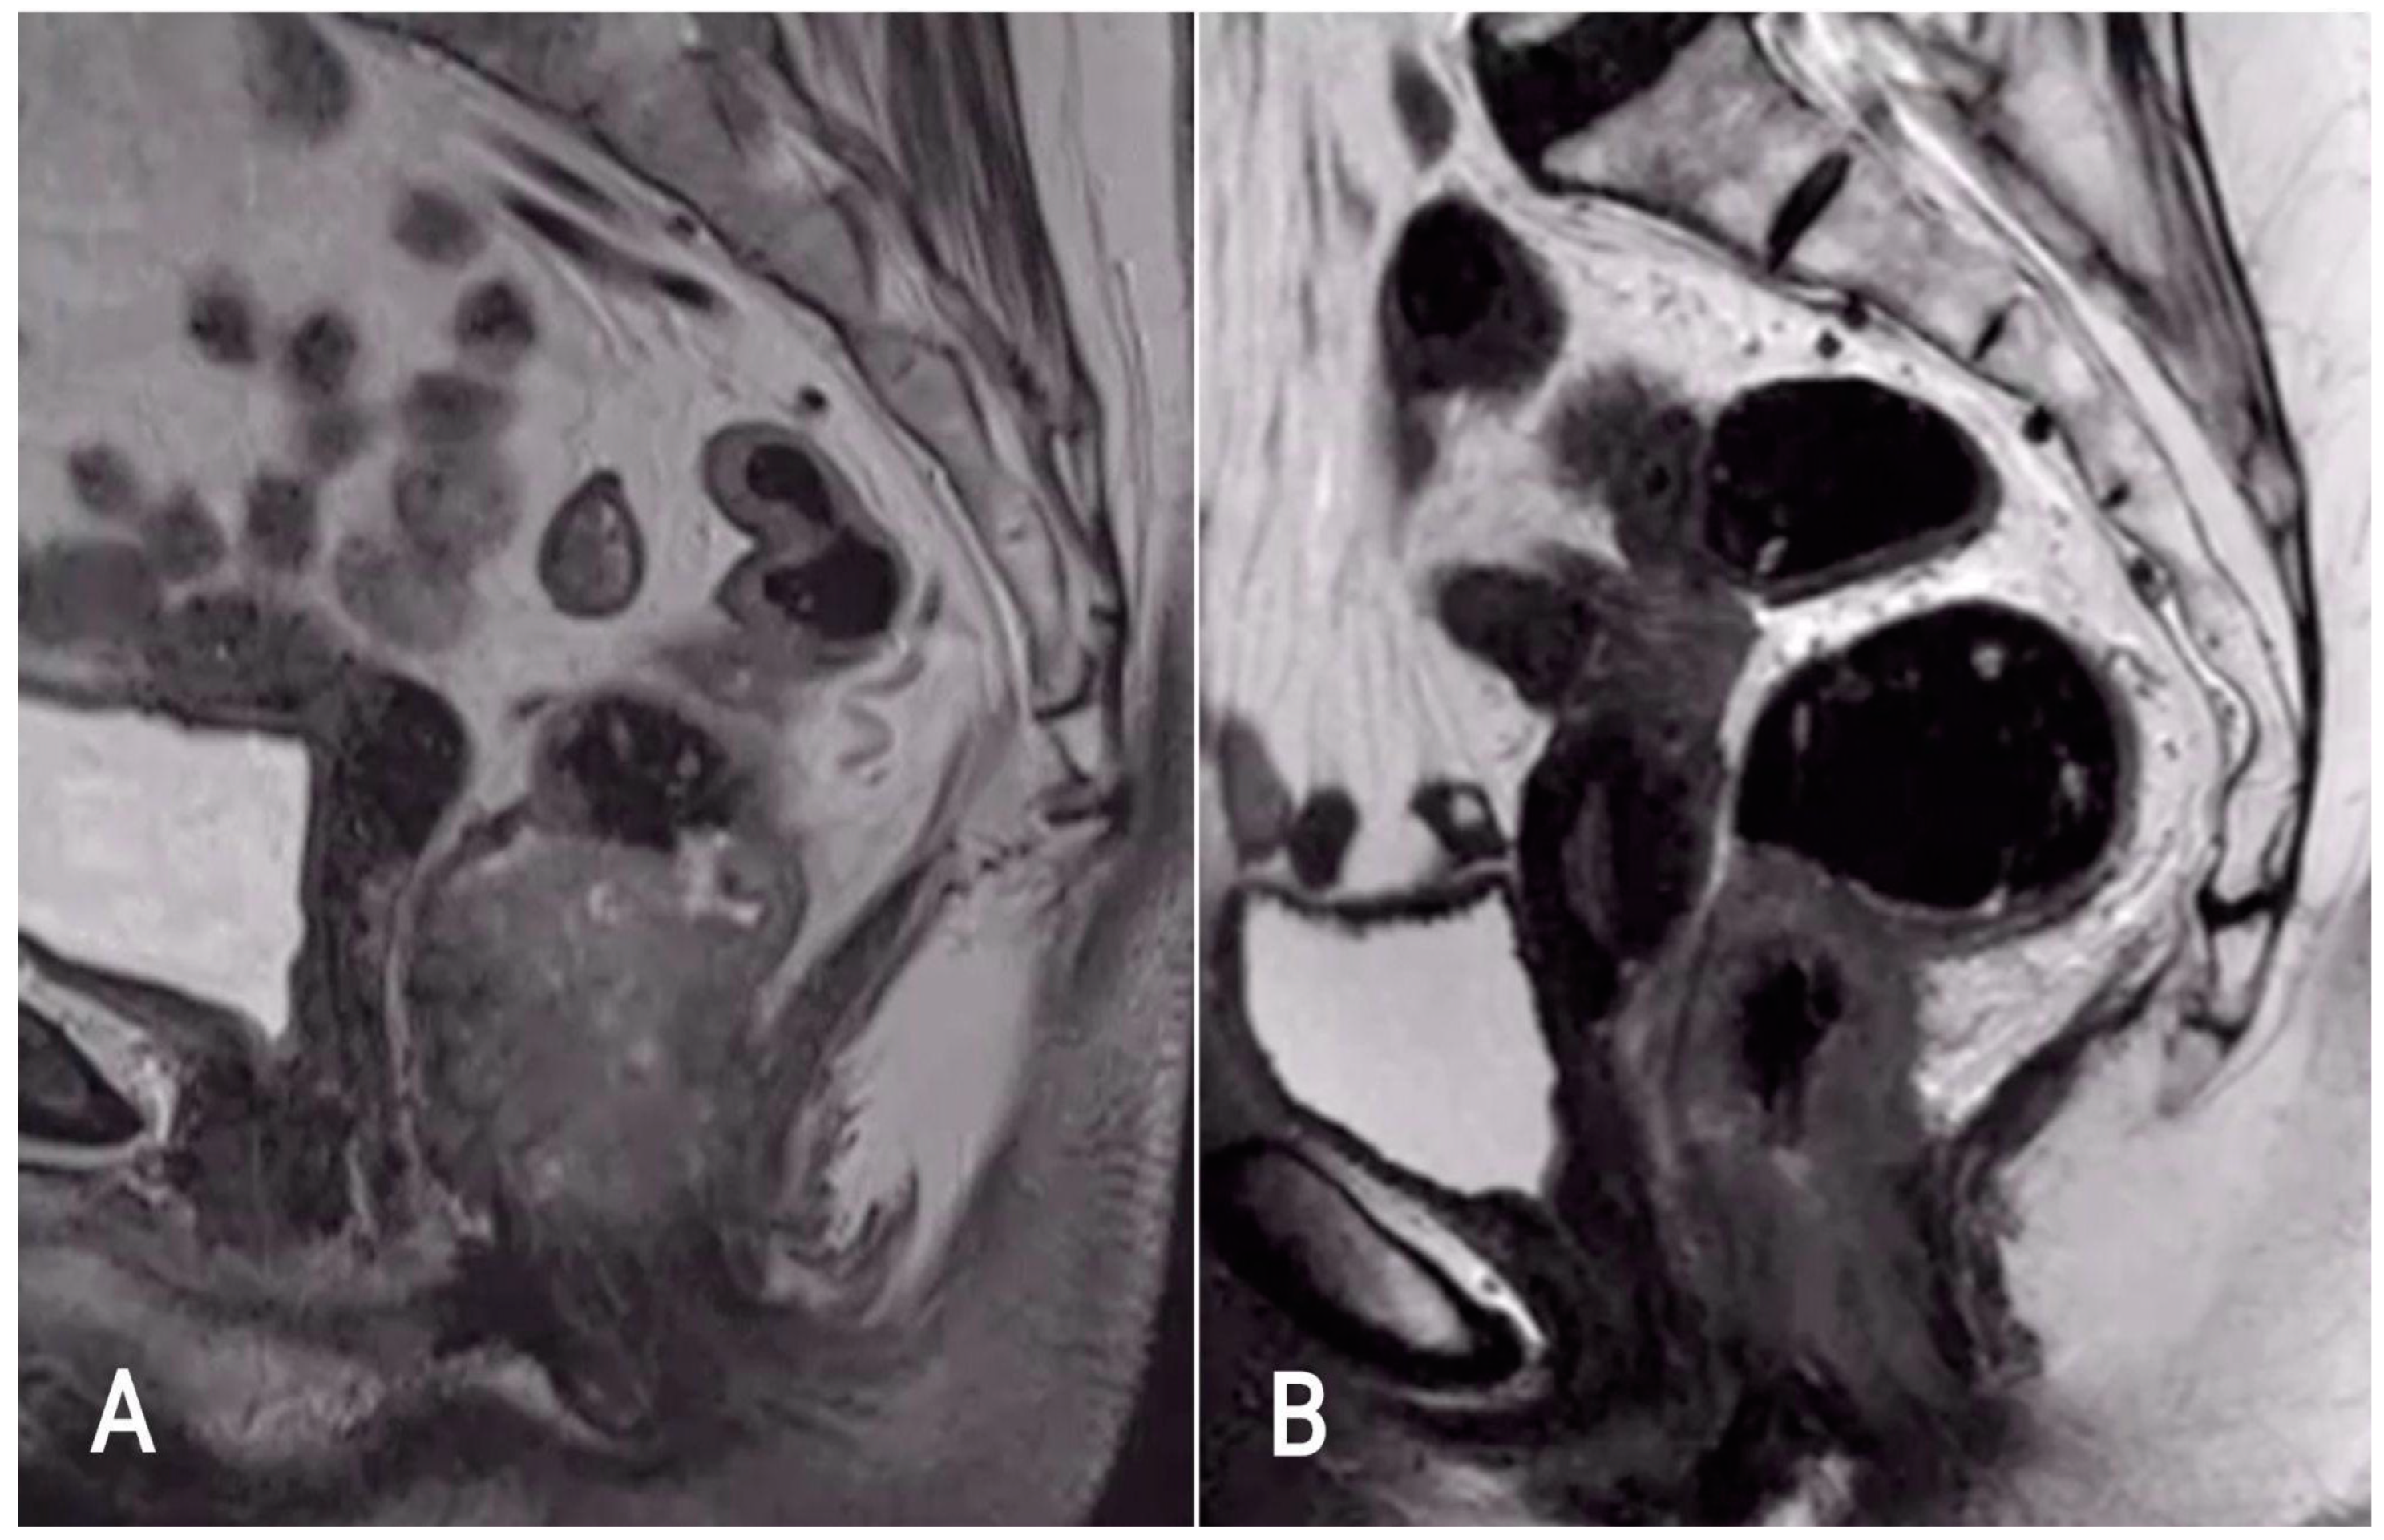

7.1. T-Staging

Evaluation after Chemoradiation Therapy